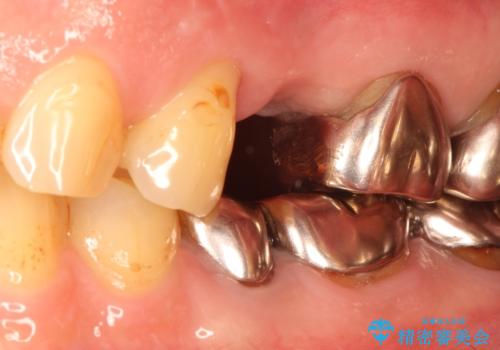

- 他院にて└5の治療を繰り返しても痛みがなくならないことを主訴に来院されました。

患歯はすでに2回の歯根切除術を受けており、長期的な予後不良となることから抜歯を選択されインプラントによる治療を行いました。

└6の不良補綴物も認め、根管治療及び補綴もやり替えてます。

インプラントによる治療は隣在歯を削らずに咬合回復できるという利点があります。

セラミッククラウンにより自然な見た目で修復できました。